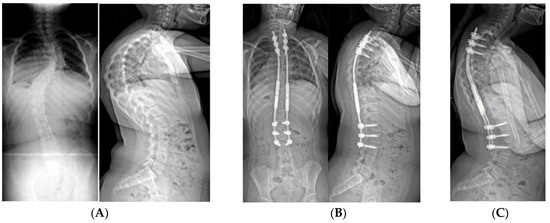

Figure 6.

(A) 10-year-old female with PWS UPD type with 85° kyphosis, a 66° right thoracic and 61° left thoracolumbar curve. (B) Expandable, magnetically actuated rods are implanted from T2–L3, reducing her scoliotic curves to 25° or less, and her kyphosis to 48°. (C) 6 months post-operatively with developing proximal junctional kyphosis. Kyphosis now measures 81°.

Figure 7.

(A) 11-year-old female with PWS UPD type with 70° scoliosis, and 60° kyphosis. (B) Same patient at 12 years of age, after T2–L2 posterior spinal fusion. Overall kyphosis measures 50°. (C) Same patient at 3 years post-operatively with 60° distal junctional kyphosis.

Figure 8.

(A) AP and lateral radiographs of a 10-year-old female with PWS deletion type with 103° curve. (B) AP and lateral radiographs 1 month later, after placement of non-fusion spinal instrumentation. Curve is 57°. (C) 18 months later, after 50mm of lengthening, curve is 25°.

Figure 9.

(A) 15-year-old female with PWS UPD type with 67° left thoracic and 60° right lumbar curve. She had thoracic kyphosis of 79° and lumbar lordosis of 84°. (B) Same patient at 4 years after T4–L3 posterior spinal fusion. The thoracic curve measures 12°, the lumbar 25° with 75° kyphosis.